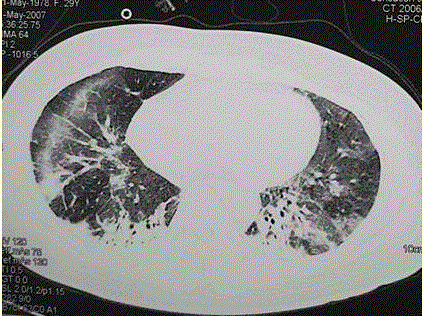

问题 患者女,29岁。间断干咳10年余,加重4个月,伴进行性呼吸困难1个月。病程中出现双手及双足非凹陷性肿胀、双侧膝关节及双侧肘关节对称性肿痛,面部出现细小红色丘疹。体检:T 36.5℃,P 88次/min,R 22次/min,BP 110/75 mmHg,SpO 93%(自然)。额部、前胸及后背散在红色小丘疹,双肺呼吸音增强,双肺中下肺野可闻及爆裂音,右肺明显。胸部CT 如图所示。 为明确诊断应检查的项目包括

选项 A.血常规 B.肺功能检查,包括通气及弥散功能检查 C.军团菌尿抗原测定 D.肺癌筛查 E.经皮肺活检 F.支气管镜检查 G.痰涂片抗酸染色 H.痰培养+药敏

答案 ABCEFH